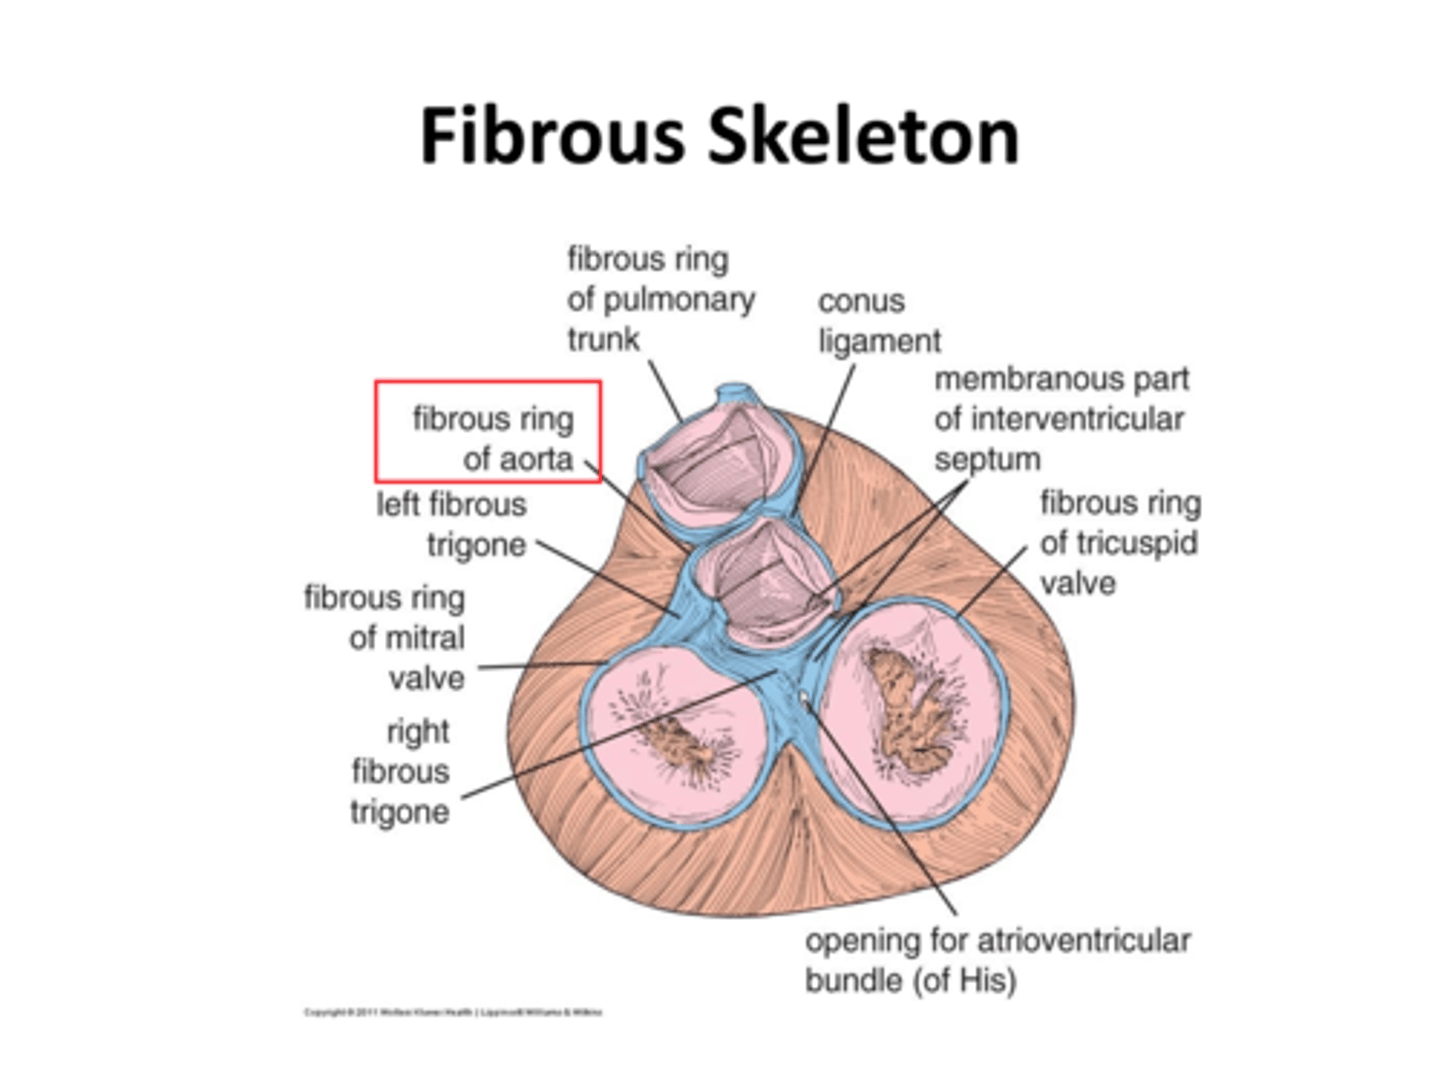

Co tworzy szkielet serca?

tkanka łączna zbita

Jaka jest rola szkieletu serca?

jest miejscem przyczepu mięśniówki przedsionków i komór oraz zastawek

Jakie są elementy szkieletu serca?

4 pierścienie włókniste

2 trójkąty włókniste

część błoniasta przegrody międzykomorowej

Jakie pierścienie włókniste wyróżniamy?

pierścień włóknisty pnia płucnego

pierścień włóknisty aorty

pierścień włóknisty przedsionkowo-komorowy prawy i lewy

pierścień włóknisty pnia płucnego

pulmonary ring (fibrous ring of pulmonary valve)

Gdzie znajduje się pierścień włóknisty pnia płucnego?

z przodu

pierścień włóknisty aorty

aortic ring (fibrous ring of aorta)